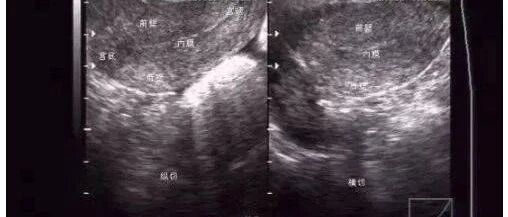

子宫内膜回声不均是怎么回事?

来源:付虹大夫

时间:2020-08-22